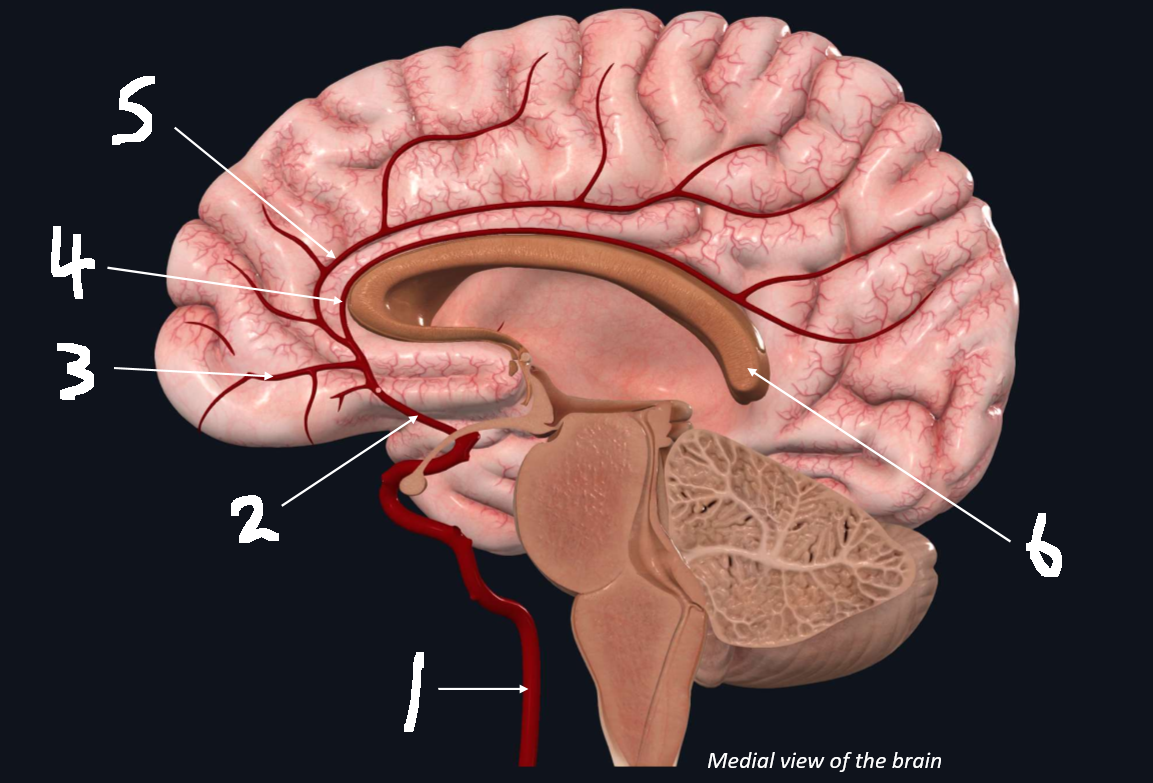

What is 1?

internal carotid artery

What is 2?

anterior cerebral artery

What is 3?

frontopolar artery

What is 4?

pericallosal artery

What is 5?

callosomarginal artery

What is 6?

corpus callosum